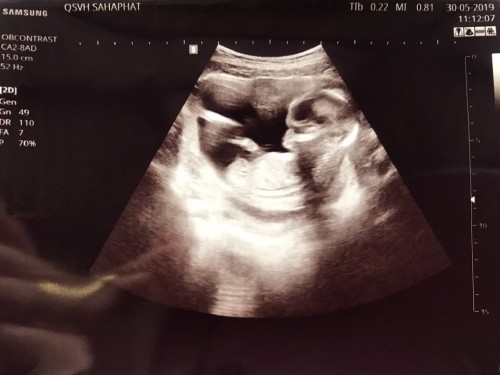

12 week 1 วันค่า เพิ่งซาวด์มาเมื่อวานเลยค่ะดิ้นเก่งมาก🥰